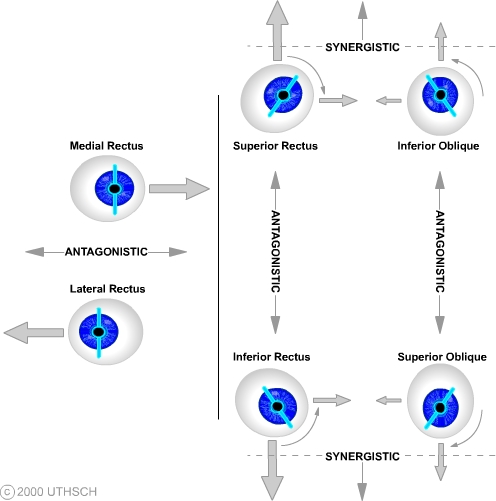

Ocular Motor Control (Section 3, Chapter 8) Neuroscience Online: An

nba.uth.tmc.edu

nba.uth.tmc.edu

eye muscles extraocular actions ocular control motor synergistic right their pull antagonistic directions direction medical same section anatomy

Eye muscles extraocular actions ocular control motor synergistic right their pull antagonistic directions direction medical same section anatomy. Lateral eye movement although a horizontal, frontal dipole is the key. Extraocular muscle actions: eye movements, rectus muscles, oblique